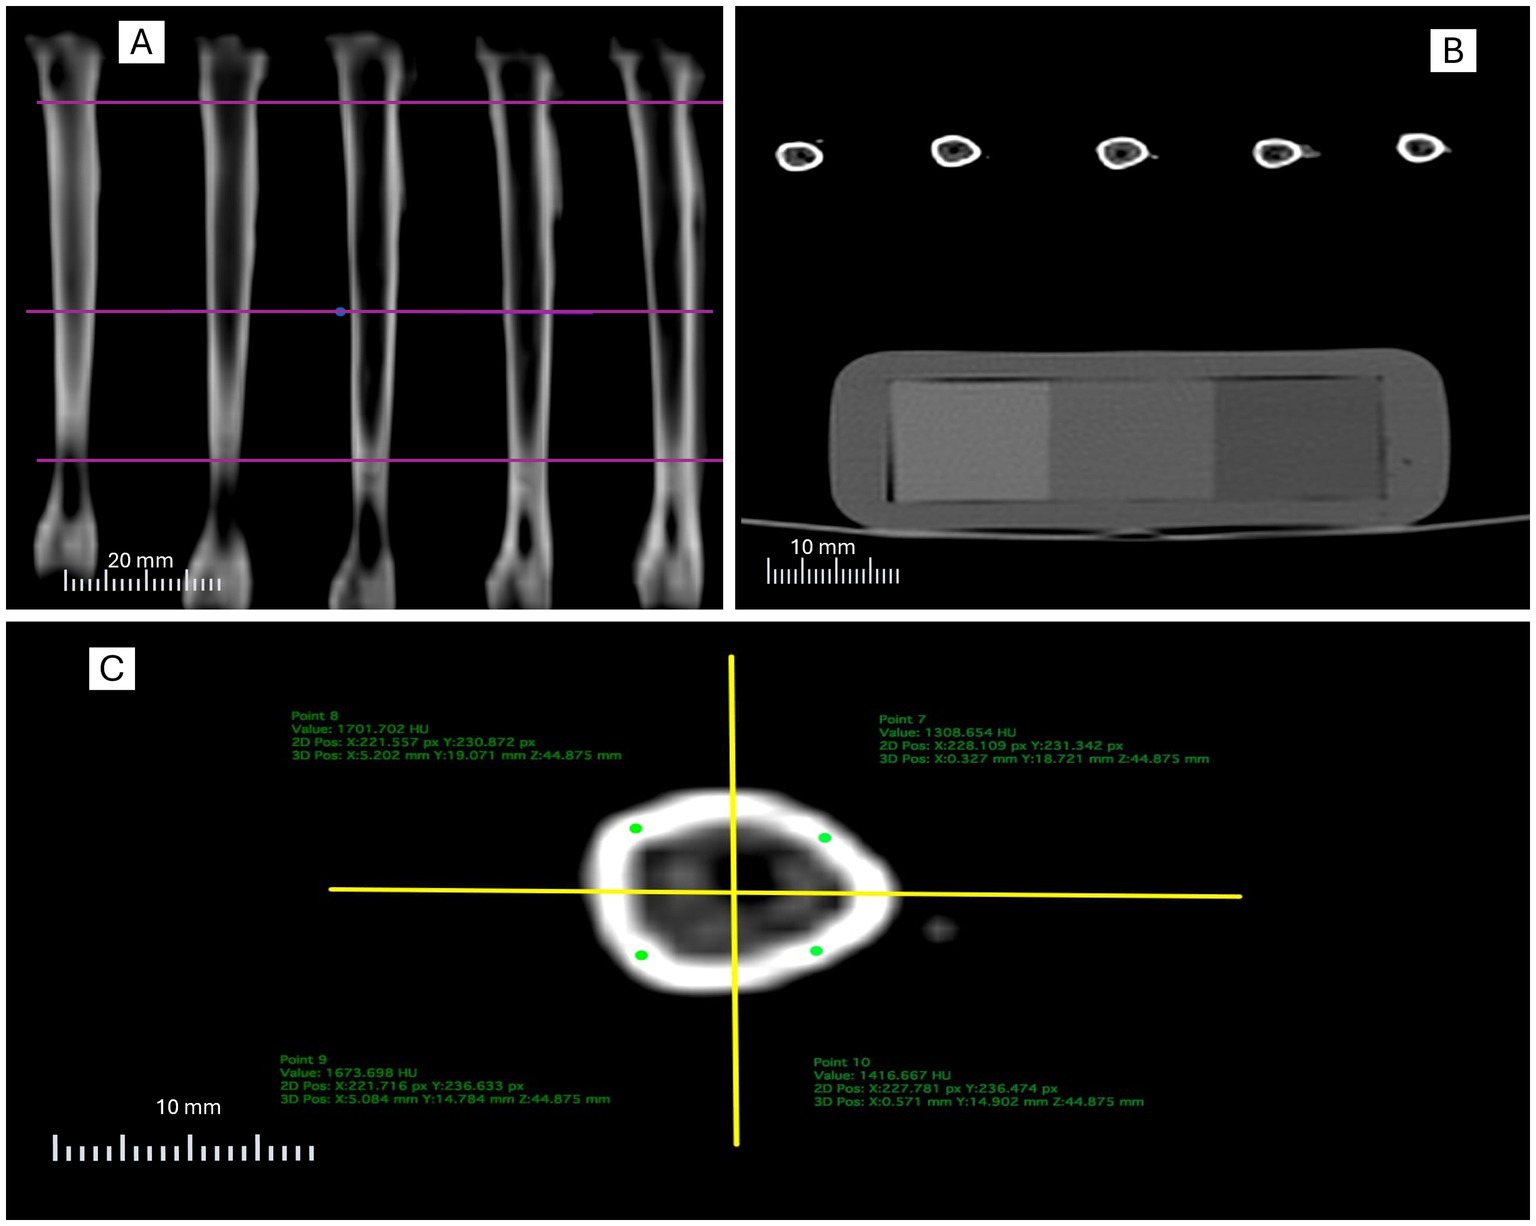

Bone quality is essential for the health, welfare, and productivity of laying hens and can be accurately assessed through quantitative computed tomography (QCT) for bone mineral density (BMD). This study compared two QCT-based methodologies for tibial BMD evaluation in 48 Dekalb White hens aged 48 weeks and examined their correlations with bone composition and eggshell quality. Method 1 (M1) analyzed four cortical quadrants as regions of interest, whereas Method 2 (M2) applied semi-automatic segmentation of the entire bone area using predefined density thresholds. Results showed a moderate correlation (r = 0.6822, p < 0.001) but low concordance (CCC = 0.120) between methods, with M1 overestimating BMD. Mean BMD values were 1152.49 ± 218.54 and 711.22 ± 118.4milligrams of hydroxyapatite per cubic centimeter (mgHA/cm³) for M1 and M2, respectively. M1 showed only mild correlations with bone parameters, such as bone weight (R² = 0.423, p = 0.038) and volume (R² = 0.086, p = 0.043), and weak or no associations with eggshell traits. In contrast, M2 exhibited stronger relationships with bone composition (bone weight: R² = 0.789, p = 0.003; bone volume: R² = 0.535, p = 0.010) and significant negative correlations with eggshell weight (R² = –0.741, p = 0.009), thickness (R² = –0.617, p = 0.017), and breaking strength (R² = –0.654, p = 0.048). Overall, M2 provided more accurate and biologically meaningful BMD estimates than M1, supporting its use for future QCT-based bone assessment in laying hens.